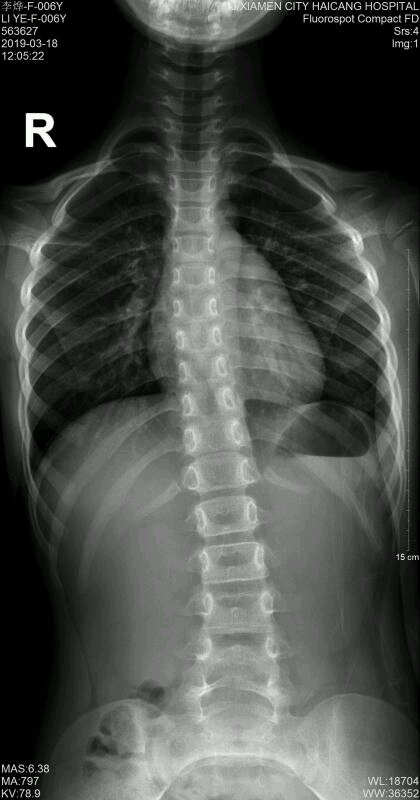

6岁的孩子,前两天查的,怎么办,快崩溃了